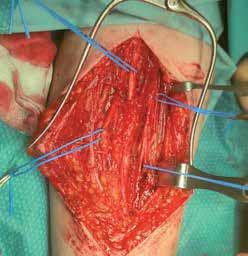

Pierwszy etap dwuetapowej rekonstrukcji ścięgna palca małego. Zygzakowate cięcie skórne. Nerwy palcowe w trakcie zespalania (żółte wskaźniki). Silikonowa proteza ścięgna wsunięta w zachowane troczki zginaczy (niebieskie wskaźniki).